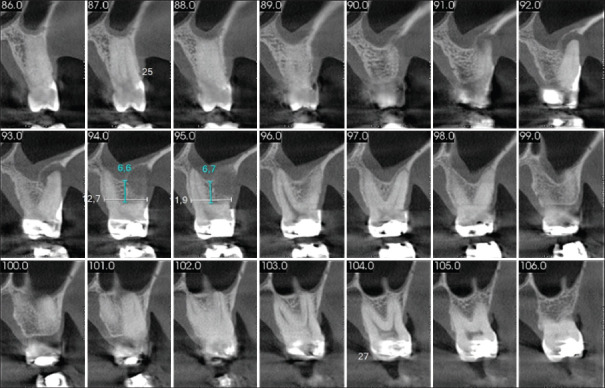

牙齿分叉缺陷的牙周治疗是具有挑战性的,因为该区域的复杂解剖结构。切除技术,如根切除,可以有效地治疗牙齿缺损,如果有适当的指示,可以导致令人满意的存活率和良好的预后。本报告描述了使用根切除结合再生手术治疗上磨牙II级分叉缺陷。再生过程包括使用冻干骨移植物结合使用胶原膜和结缔组织移植物。24个月的随访证明了治疗的成功,临床附着水平增加,探测袋深度减少,断层图像显示新硬膜层的形成。一个健康和稳定的牙周组织可以通过正确的应用更保守的技术来保护牙齿。

Periodontal treatment of teeth with furcation defects is challenging due to the complex anatomy of the area. Resective techniques, such as root resection, may be effective in managing teeth with this defect if appropriately indicated and can lead to satisfactory survival rates associated with a favorable prognosis. This report describes the treatment of a Class II furcation defect in an upper molar using root resection combined with regenerative procedures. The regenerative procedure involved the use of a lyophilized bone graft combined with the use of a collagen membrane and a connective tissue graft. The 24-month follow-up demonstrated the success of the therapy, with a gain in clinical attachment level, a reduction in probing pocket depth, and a tomographic image showing the formation of new lamina dura. A healthy and stable periodontium can be achieved through the correct application of more conservative techniques aimed at preserving the dental element.